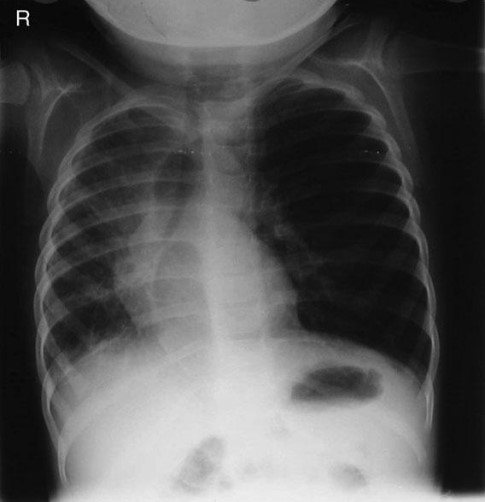

Common X-ray Findings: